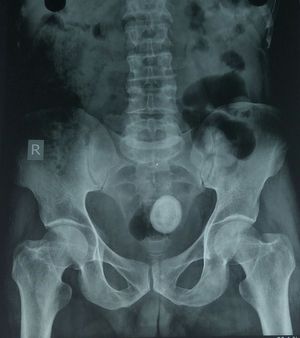

Differential diagnosis ??

Vesicolithiasis?

Vesicolithiasis. Calcific myoma of uteri

Sorry, but this looks a condom..

Bladder carcinoma